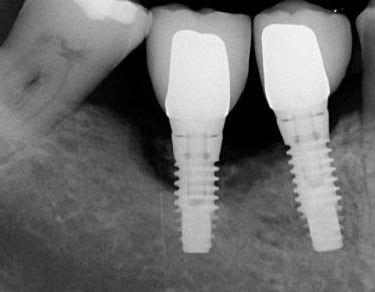

Le temps de cicatrisation d’un implant dentaire varie généralement entre 2 et 6 mois. Cette période permet l’ostéointégration, c’est-à-dire la fusion de l’implant avec l’os. Elle dépend de la qualité osseuse, de l’hygiène bucco-dentaire et du respect des recommandations post-opératoires données par le chirurgien-dentiste.

Implant dentaire durée de vie

La durée de vie d’un implant dentaire est généralement de 15 à 25 ans, voire davantage avec une hygiène rigoureuse et un suivi régulier chez le dentiste. Sa longévité dépend de la qualité osseuse, du mode de vie (tabac, bruxisme) et d’un entretien quotidien adapté pour prévenir toute inflammation péri-implantaire.